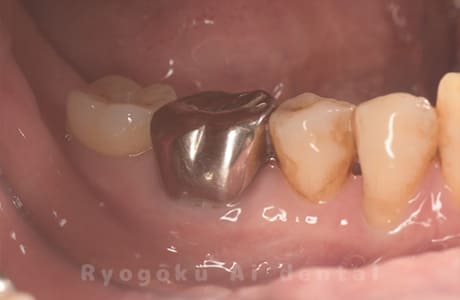

Case12

-

- 原因

- 左下7番歯牙破折

- 治療内容

- インプラント治療

- 治療費用

- 約600,000円

左下の奥歯が痛いとのことでご来院された患者様です。歯が完全に割れており、保存が不可能であったため、抜歯を行い、その際に骨に変わるお薬を入れ、十分な治癒を待ってからインプラント治療を行いました。経過良好で、大変満足されました。

<リスク・副作用>

治療後、痛みや違和感、出血、腫れなどが出る事があります。喫煙者、糖尿病などの方の場合、歯が生着しない場合があります。